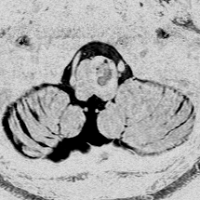

2度の延髄内出血を生じた海綿状血管腫です。でも初回の出血からすでに27年間がたちます。症状も回復して麻痺もなくていまは社会生活に困ることはありません。脳幹部の海綿状血管腫の中には1ヶ月に何回もひどい出血を繰り返すのもあるのですが,この例のように30年近い間に軽い出血が2回だけというのもあります。残念ながら正確にこれを予測することはできません。この患者さんの海綿状血管腫は手術で摘出すれば麻痺などの合併症の可能性があるのでしません。